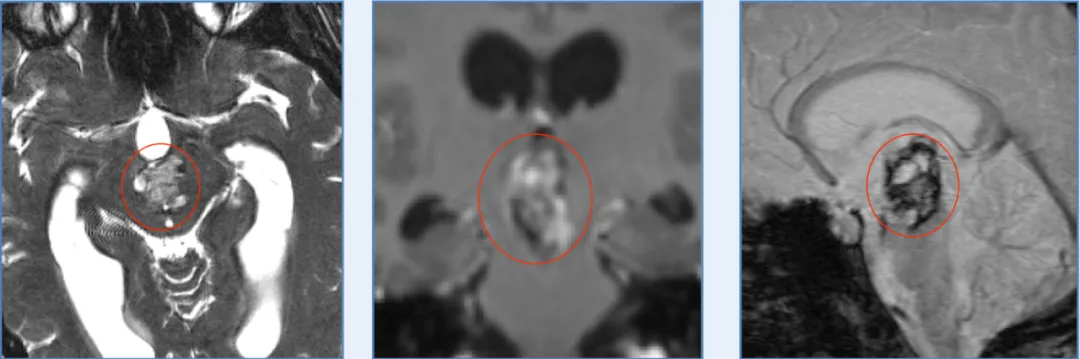

在神经外科领域,松果体区一直被称为手术的禁区。这里位于大脑最深处,血管神经错综复杂,每一步操作都如履薄冰。而海绵状血管瘤更是一种罕见的血管畸形,像一颗不定时炸弹,随时可能...